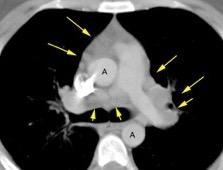

En el normal, el bronquio intermediario (BI) aparece en la proyección lateral, como una línea fina vertical que cruza el bronquio del LSI en su unión con el principal. (BPI) Engrosamiento del bronquio intermediario (BI)

97% de normales

Causas

Fallo cardiaco

Ca de pulmón

Metástasis

Linfoma

Sarcoidosis

Castleman

Schnur MJ et al.. Thickening of the Posterior Wall of the Bronchus Intermedius. Radiology. 1981

MJ et al.. Thickening of the Posterior Wall of the Bronchus Intermedius. Radiology. 1981 Ca. microcítico